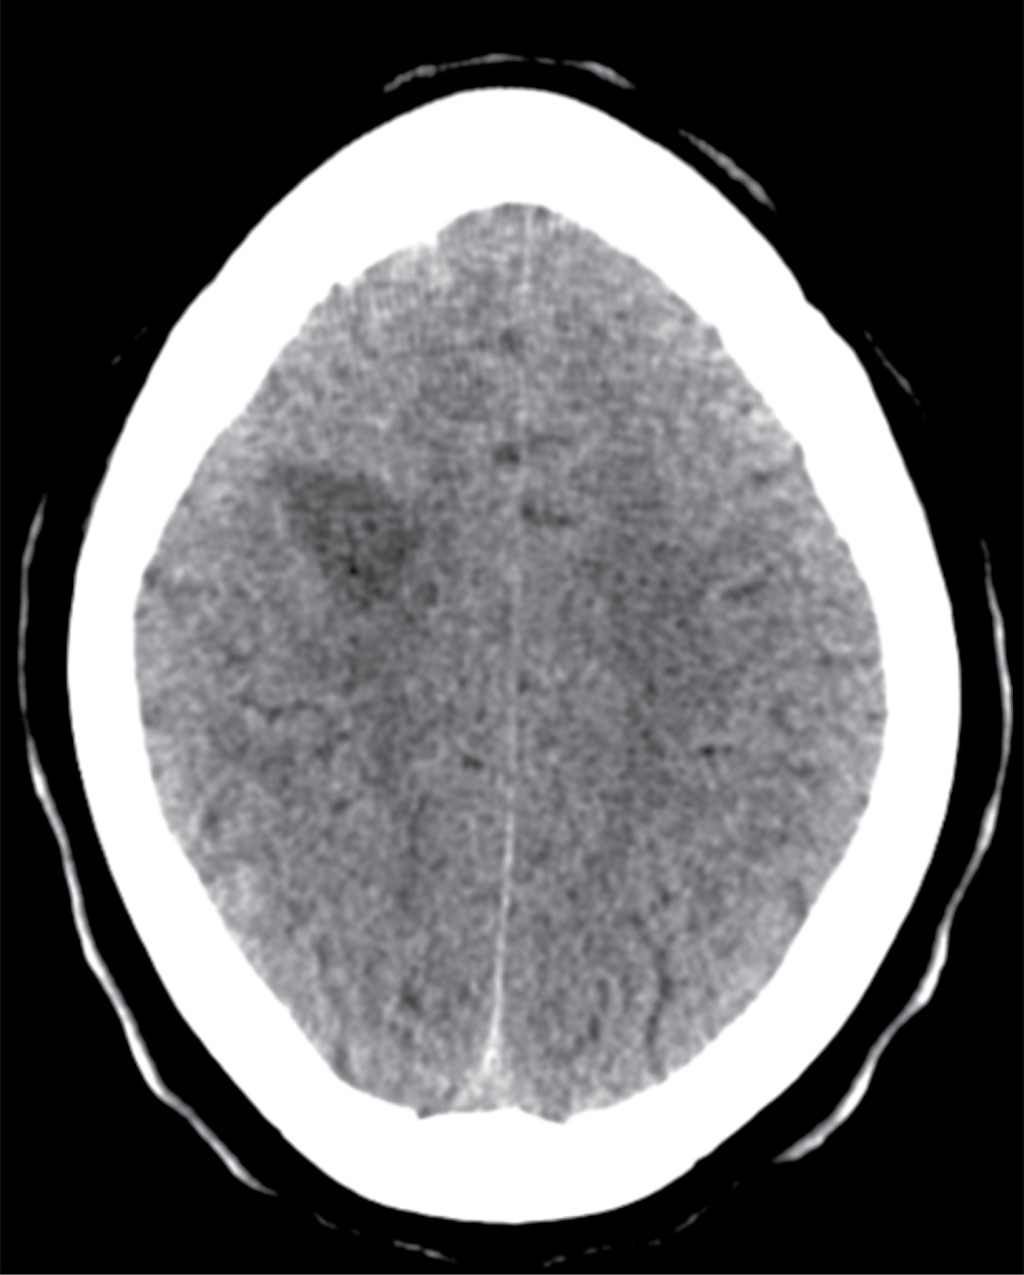

Se realizó una tomografía axial computarizada (TAC) cerebral en la que se observaron numerosas áreas hipodensas frontoparietales derechas, temporoparietales izquierdas y cerebelosas bilaterales que no realzaron tras la administración de contraste y eran compatibles con regiones de encefalitis (Figura 1).

La biopsia se considera el estándar de oro para realizar el diagnóstico definitivo, pero debido a que las lesiones se encuentran en la mayoría de las ocasiones en localizaciones profundas y de difícil acceso, se opta por utilizar técnicas de neuroimagen (TAC o RM) y comenzar tratamiento empírico previo a la confirmación microbiológica. En la TAC se visualizan lesiones únicas o múltiples de aspecto hipodenso, habitualmente con edema perilesional de gran cuantía que pueden condicionar un efecto masa y con captación de contraste muestran un patrón de anillo con edema perilesional en ganglios basales (48%), lóbulo frontal (37%) y parietal (37%).8